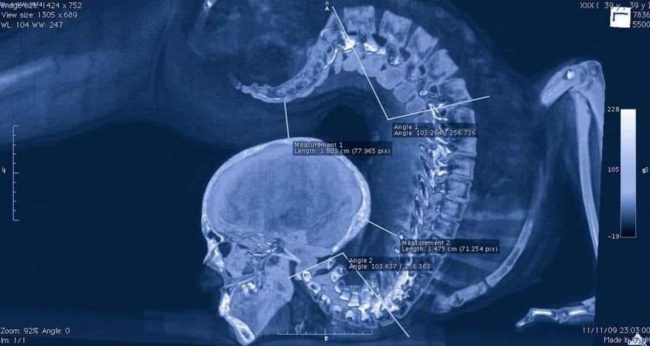

Details